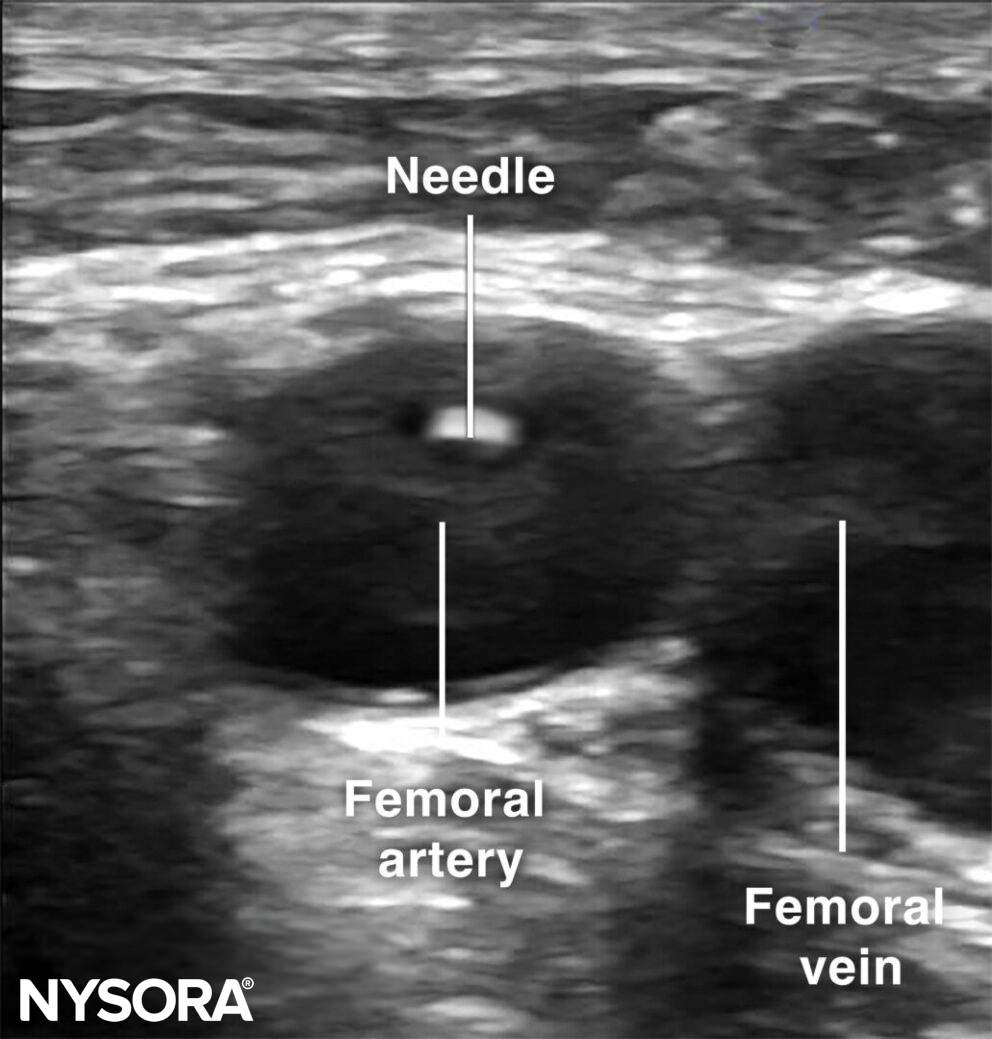

The out-of-plane technique is the most commonly used technique for arterial vascular access. Before the actual puncture, scan dynamically to get an idea of the artery’s direction. Use the creep technique to follow the needle tip at all times.

Out-of-plane cannulation of the femoral artery.